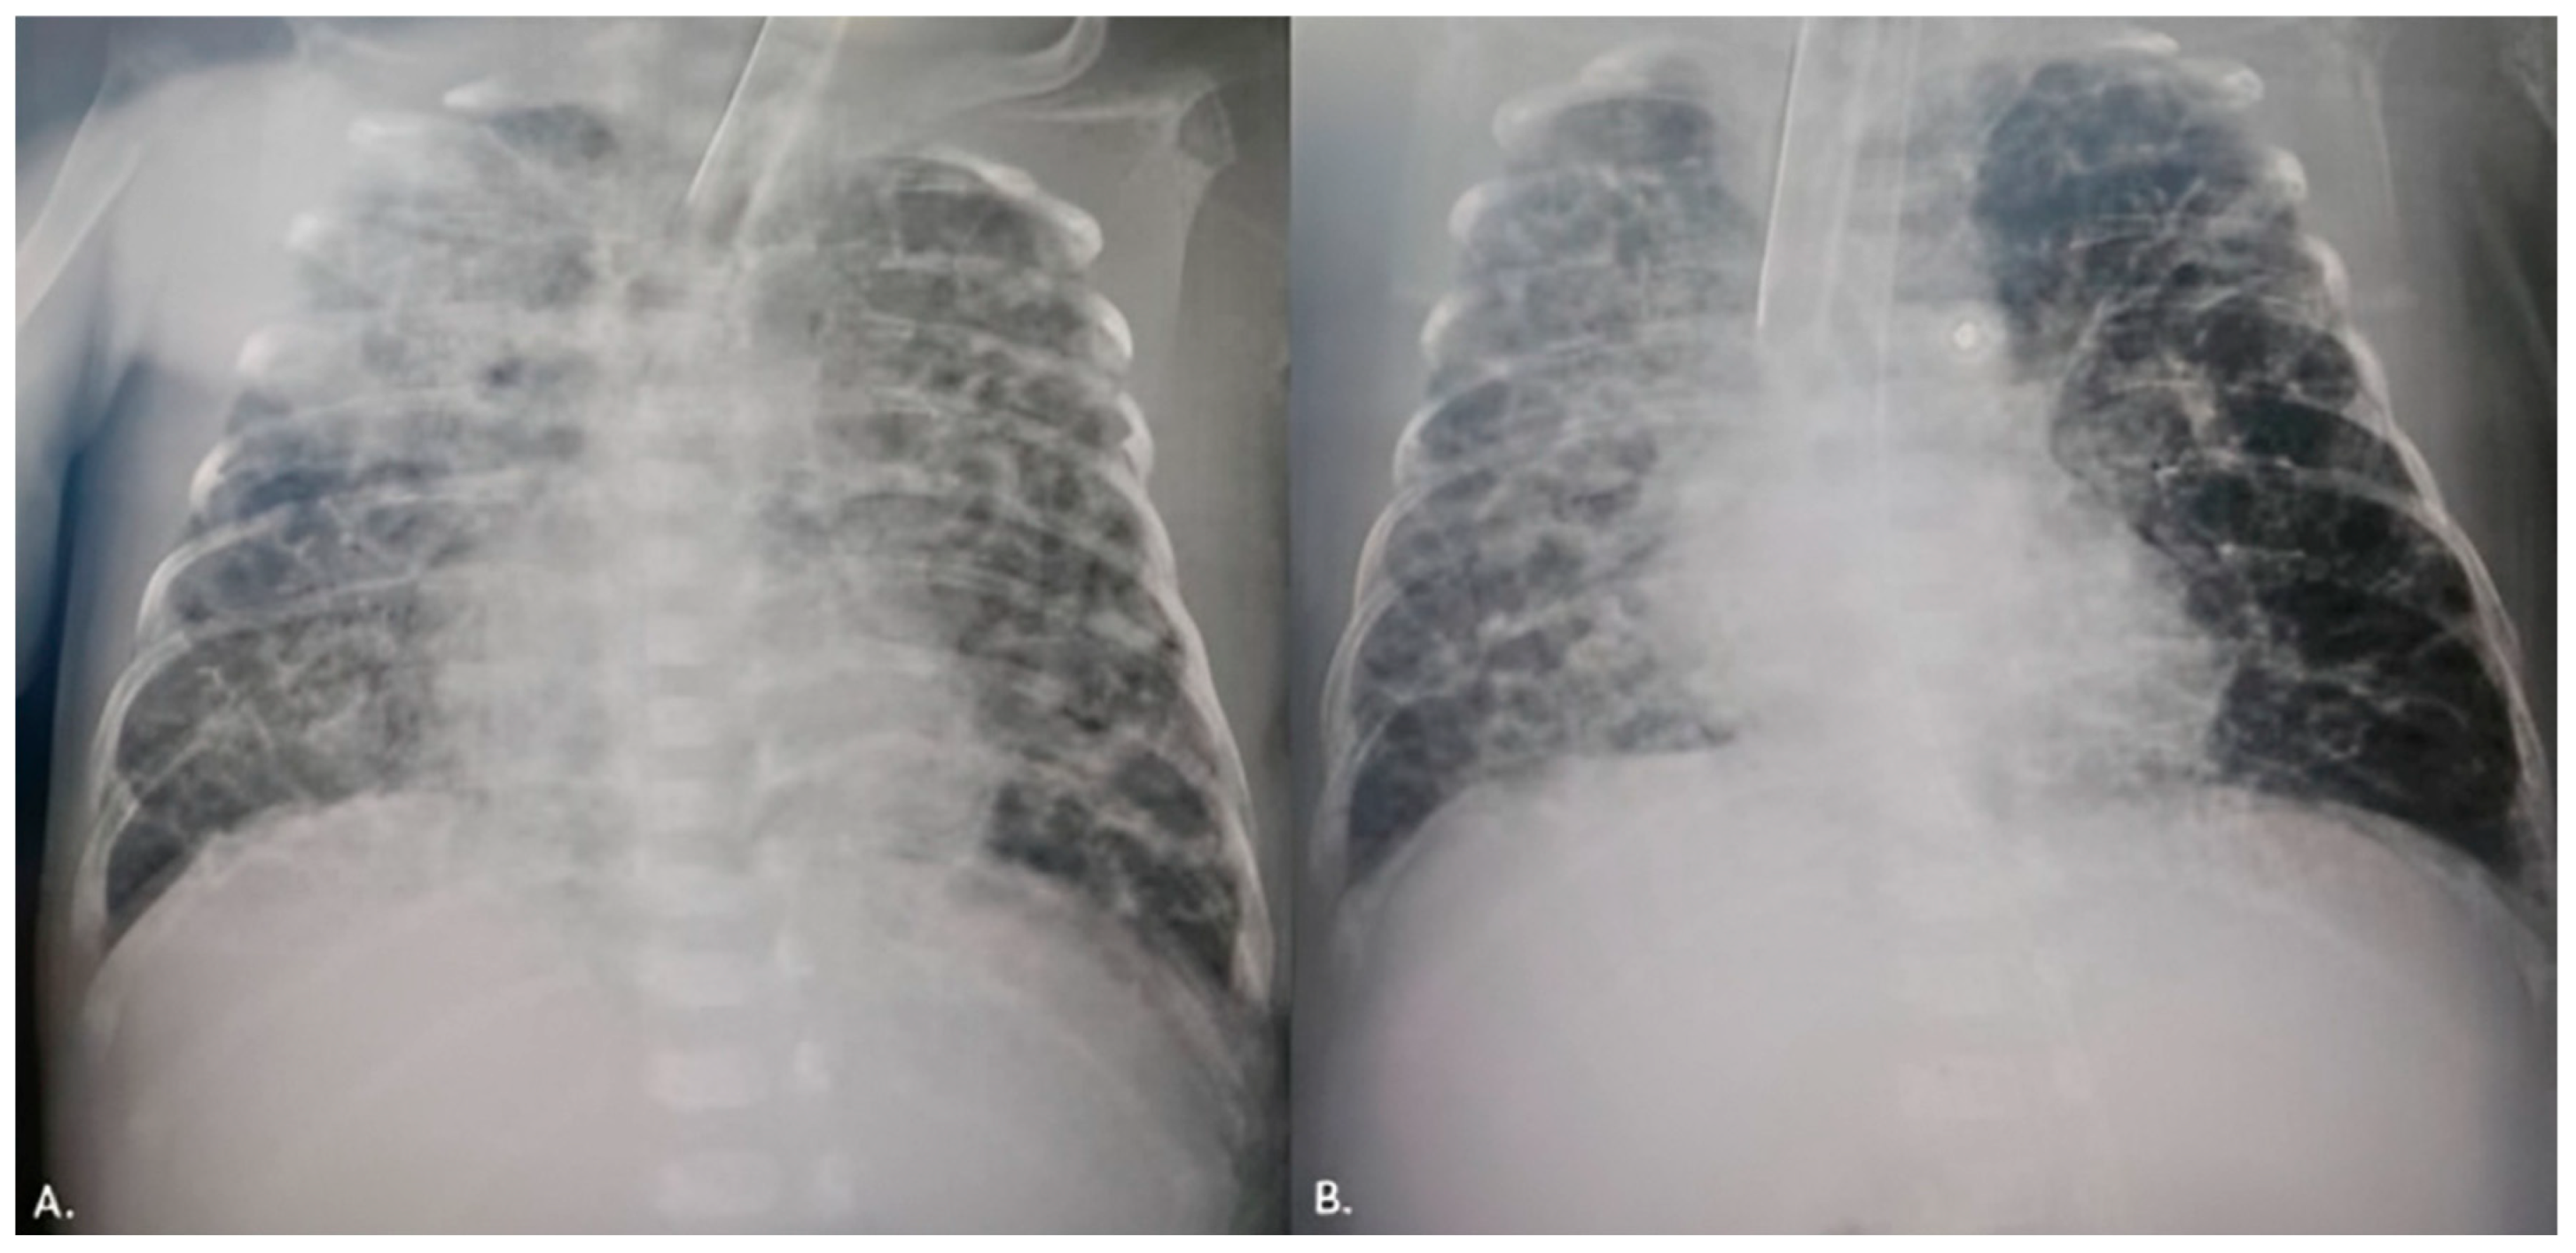

Due to the maintenance of the hsPDA and in addition to the applied therapy, a transfer to our Institute for further treatment was indicated. Upon admission, the patient was hypotrophic (weight 1170 g), on mechanical ventilation, normotensive, but oliguric, with signs of acute renal impairment manifested by elevated urea and creatinine levels (maximum up to 18.4 mmol/L and 90 μmol/L (ref. range 3.3–7.5 mmol/L and <55 μmol/L, respectively). TTE examination revealed a widely open PDA, 2.3 mm in diameter on the pulmonary end (2.1 mm/kg) and 8 mm long (Figure 1a,b). The left atrial to the aortic root (LA/Ao) ratio was 1.8, and the end-diastolic left ventricle diameter Z score was +2.89. The reversal of forward flow in the renal arteries during diastole was observed. Although the failed response to medical treatment was observed, the case was discussed in a joint cardiology–cardiothoracic (JCC) meeting, and we decided to perform transcatheter PDA closure using the Amplatzer Piccolo Occluder (APO) (Abbott Structural Heart, Plymouth, MN, USA) from the pulmonary arterial end.

The intervention was performed in a catheterization room under general anesthesia. The neonatal transport team transferred the patients to the Cath Lab. Both patients were on mechanical ventilation, so the position of the ETT was checked using fluoroscopy at the start of the procedure. To prevent oxygen-free radical damage to end organs, the goal oxygen saturation was 89–93% [7]. An air heater and plastic drape cover prevented hypothermia. A standard 4 Fr introducer sheath is placed in the right femoral vein using a 20-gauge needle, floppy-tipped 0.018 guide wire, and standard Seldinger technique using ultrasound guidance. The right Judkins catheter and 0.035″ Terumo guide wire were fed across the femoral vein, lower vena cava, right atrium, right ventricle, pulmonary artery, and PDA placed in the descending aorta. Across the right Judkins catheter, a 0.018′′ floppy tipped wire with a “hockey stick” curve was introduced in the aorta, and the right Judkins catheter was then exchanged for the Torqvue LP delivery catheter (Abbott, MN, USA) (0.046″). Biplane aortography [6] was performed in anteroposterior and left lateral planes [4]. The angiography (1.5 mL of contrast) revealed PDA Krichenco type E (Figure 2a) [8]. Before the aortography, a naso-gastric tube was filled with contrast to mark the aortic end of the PDA. In the first patient, the duct diameter on the pulmonary end was measured at 2.4 mm, and the length was 9 mm. In the second case, the pulmonary end diameter was 2.7 mm, and the length was 12 mm. We decided to use APO 9-PDAP-04-02-L and 9-PDAP-04-04-L, respectively. The entire device, with both retention discs, was implanted within the duct (Figure 2b). Before realizing the device, TTE pointed out adequate device position without descending aorta, left pulmonary branch obstruction, and a residual shunt (Figure 1c,d). Control angiography after the device was realized confirmed adequate APO position (Figure 2c). Prophylactic antibiotics and a heparin bolus (100 IU/kg) were administered. The intervention was uneventful; the fluoroscopy lasted 5 min, and we spent 3 mL of contrast. In the third case, epinephrine was continuously administered throughout the entire procedure.

Figure 1. (a) Echocardiography examination before patent ductus arteriosus (PDA) closure. (b) Moderate left-to-right shunt across PDA. (c,d) Echocardiography pointed out the intraductal position of the Amplatzer Piccolo Occluder.